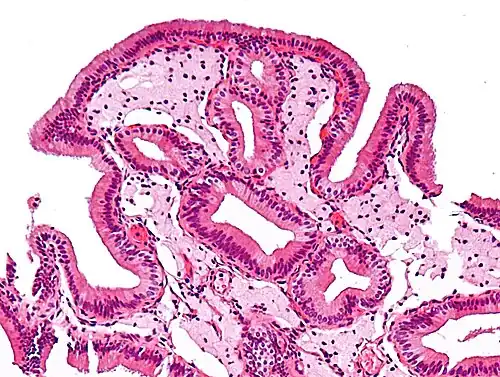

Micrograph of cholesterolosis of the gallbladder

Micrograph of cholesterolosis of the gallbladder